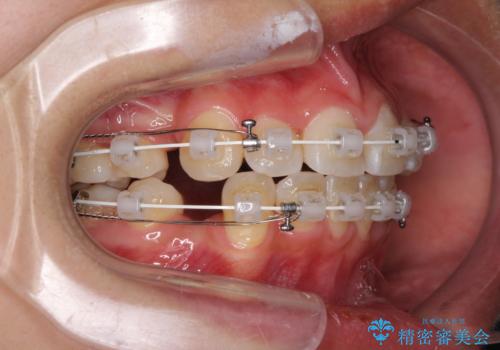

- 審美装置

叢生解消のため、上下左右第一小臼歯4本を抜歯し、ワイヤー装置にて矯正治療を行うこととしました。

半年ほどで前歯のデコボコは改善され、汚れの溜まりやすさは解消されました。

抜歯スペースを閉じるために期間がかかりましたが、当初予定通り2年強で終えることができました。